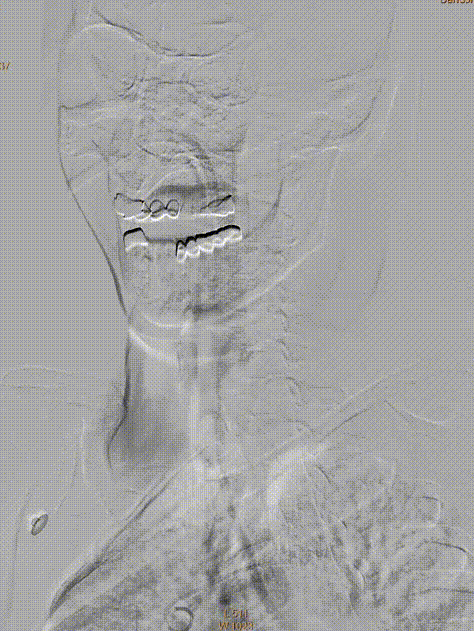

术前DSA造影(评估病变及代偿):Ⅰ型弓,左侧大脑中动脉闭塞;软脑膜动脉对其部分代偿,ASITN/SIR 1级。

术前DSA造影